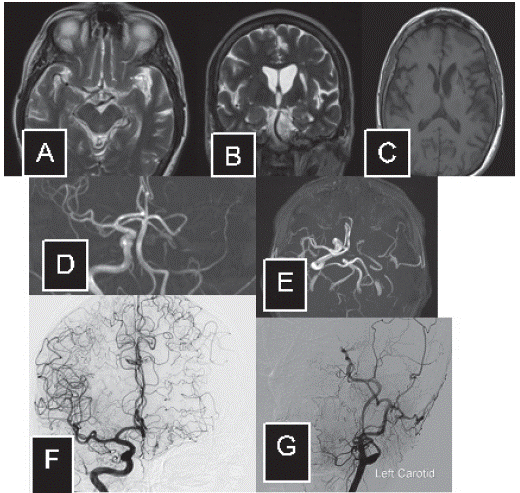

Paciente femenina con pérdida transitoria de la memoria, sin otros déficits, quien fue internada para estudios, evidenciando en imagen de resonancia magnética infarto antiguo frontal-basal izquierdo, así como una imagen de ausencia de flujo en circulación de la arteria cerebral media izquierda (figura 3 a-b). Holter de 24 horas normal, ecocardiografía transesofágica que reveló un foramen oval permeable, con dopler de miembros inferiores sin lesiones. Doppler carotideo sin alteraciones. La angiografía cerebral invasiva reveló ausencia de flujo en la arteria cerebral media del lado izquierdo con una configuración de Moyamoya compensatoria a expensas de vasos lenticuloestriados que reconstituyen las ramas corticales en ausencia de infartos (figura 3 c-d-e). La paciente ha permanecido libre de síntomas que sugieran isquemia o hemorragia cerebral.

Figura 3 Imágenes de resonancia magnética (A-B-C-D): se evidencia infarto frontal antiguo y ausencia de señal en el territorio de la arteria cerebral media y arteria comunicante anterior del lado izquierdo. Panangiografía a cerebral (E-F-G): reconstitución de la circulación del hemisferio izquierdo a expensas de ramas lenticuloestriadas neoformadas y circulación colateral.